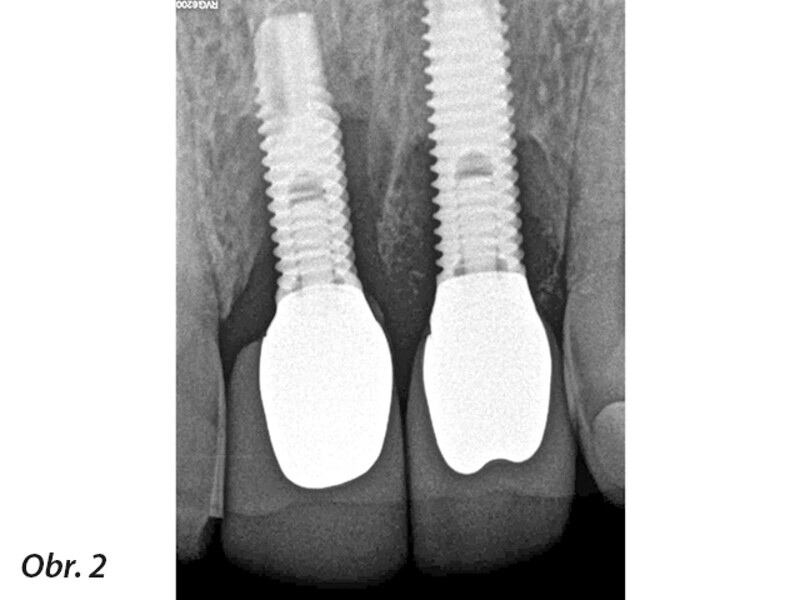

Terapie periimplantitidy při použití resorbovatelného, náhradního kostního materiálu